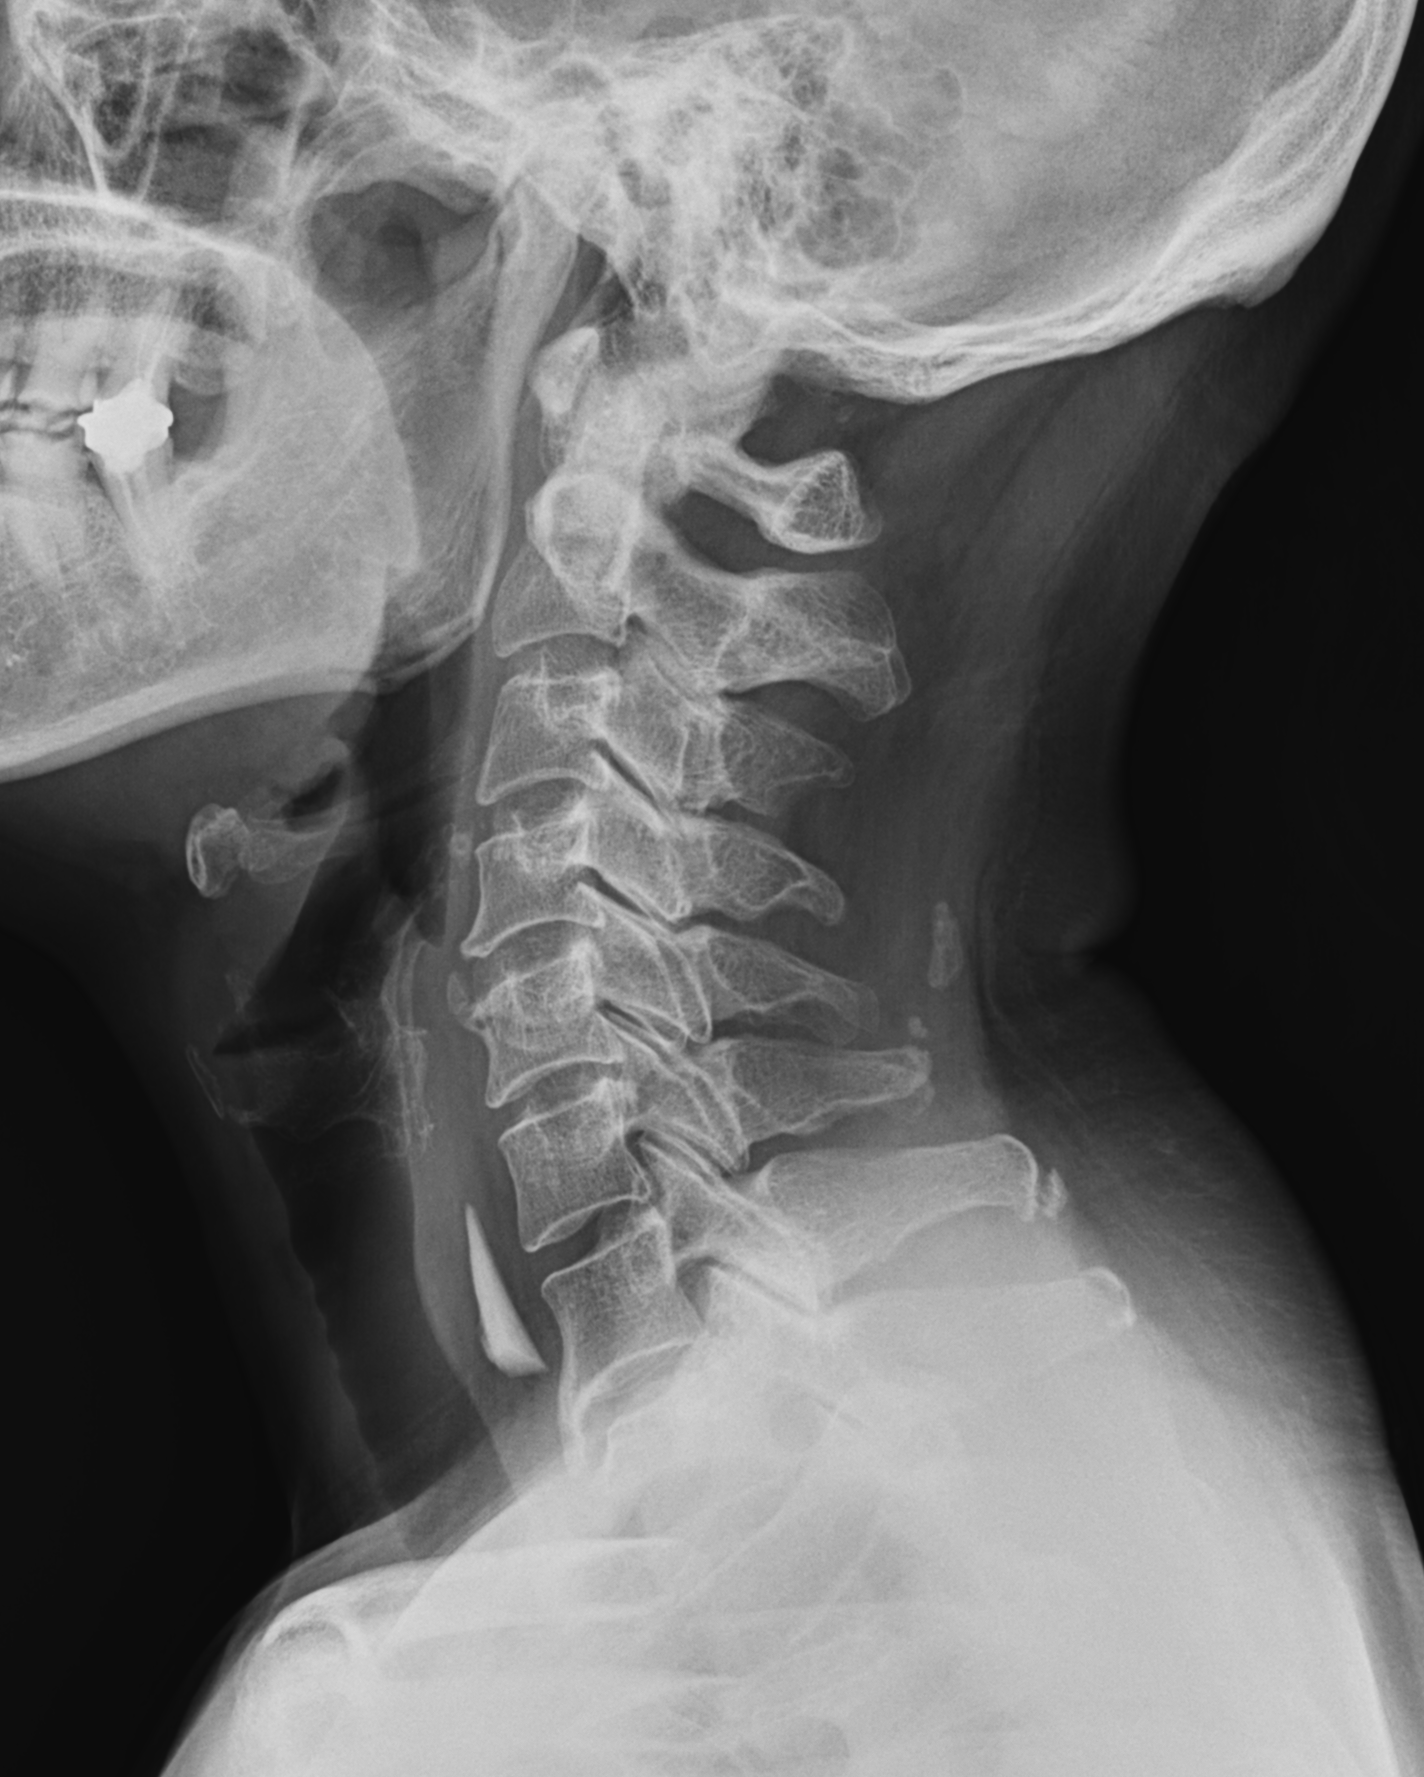

다행히 다른 x ray 영상 중 neck lateral x ray 사진에서 이물의 모양과 위치를 확인 할 수 있었다.

식도에 걸려있는 뾰족한 모양의 이물로, 환자의 증상도 심하여 빠르게 응급내시경을 의뢰하였다.